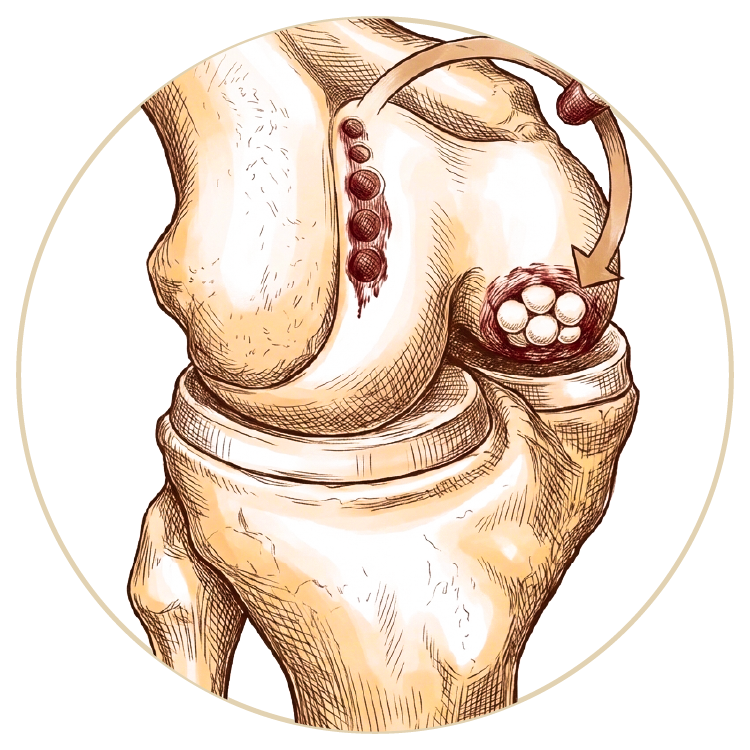

Arka Çapraz Bağ Ameliyatı

Ön Çapraz Bağ Ameliyatı

Kıkırdak Yaralanmaları